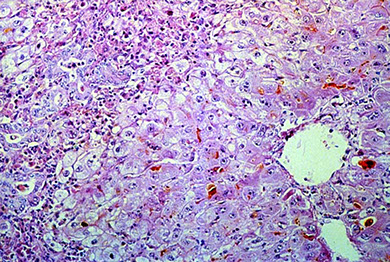

Alcoholic hepatitis

Seen in constant long-term alcoholics

Micro: Swollen and necrotic hepatocytes (balloon degeneration) c steatosis, Mallory bodies, zone 3 fibrosis and neutrophilic infiltrates

- Mallory bodies: intracytoplasmic eosinophilic inclusion bodies, stain c intermediate filament, CK8/18, p62, and ubiquitin; in hepatocytes caused by ubiquinated cytokeratin intermediate filaments

Dx: AST/ALT > 1.5, inc GGT (same as in acute viral hepatitis), dec albumin and inc globulins; prolonged clotting times